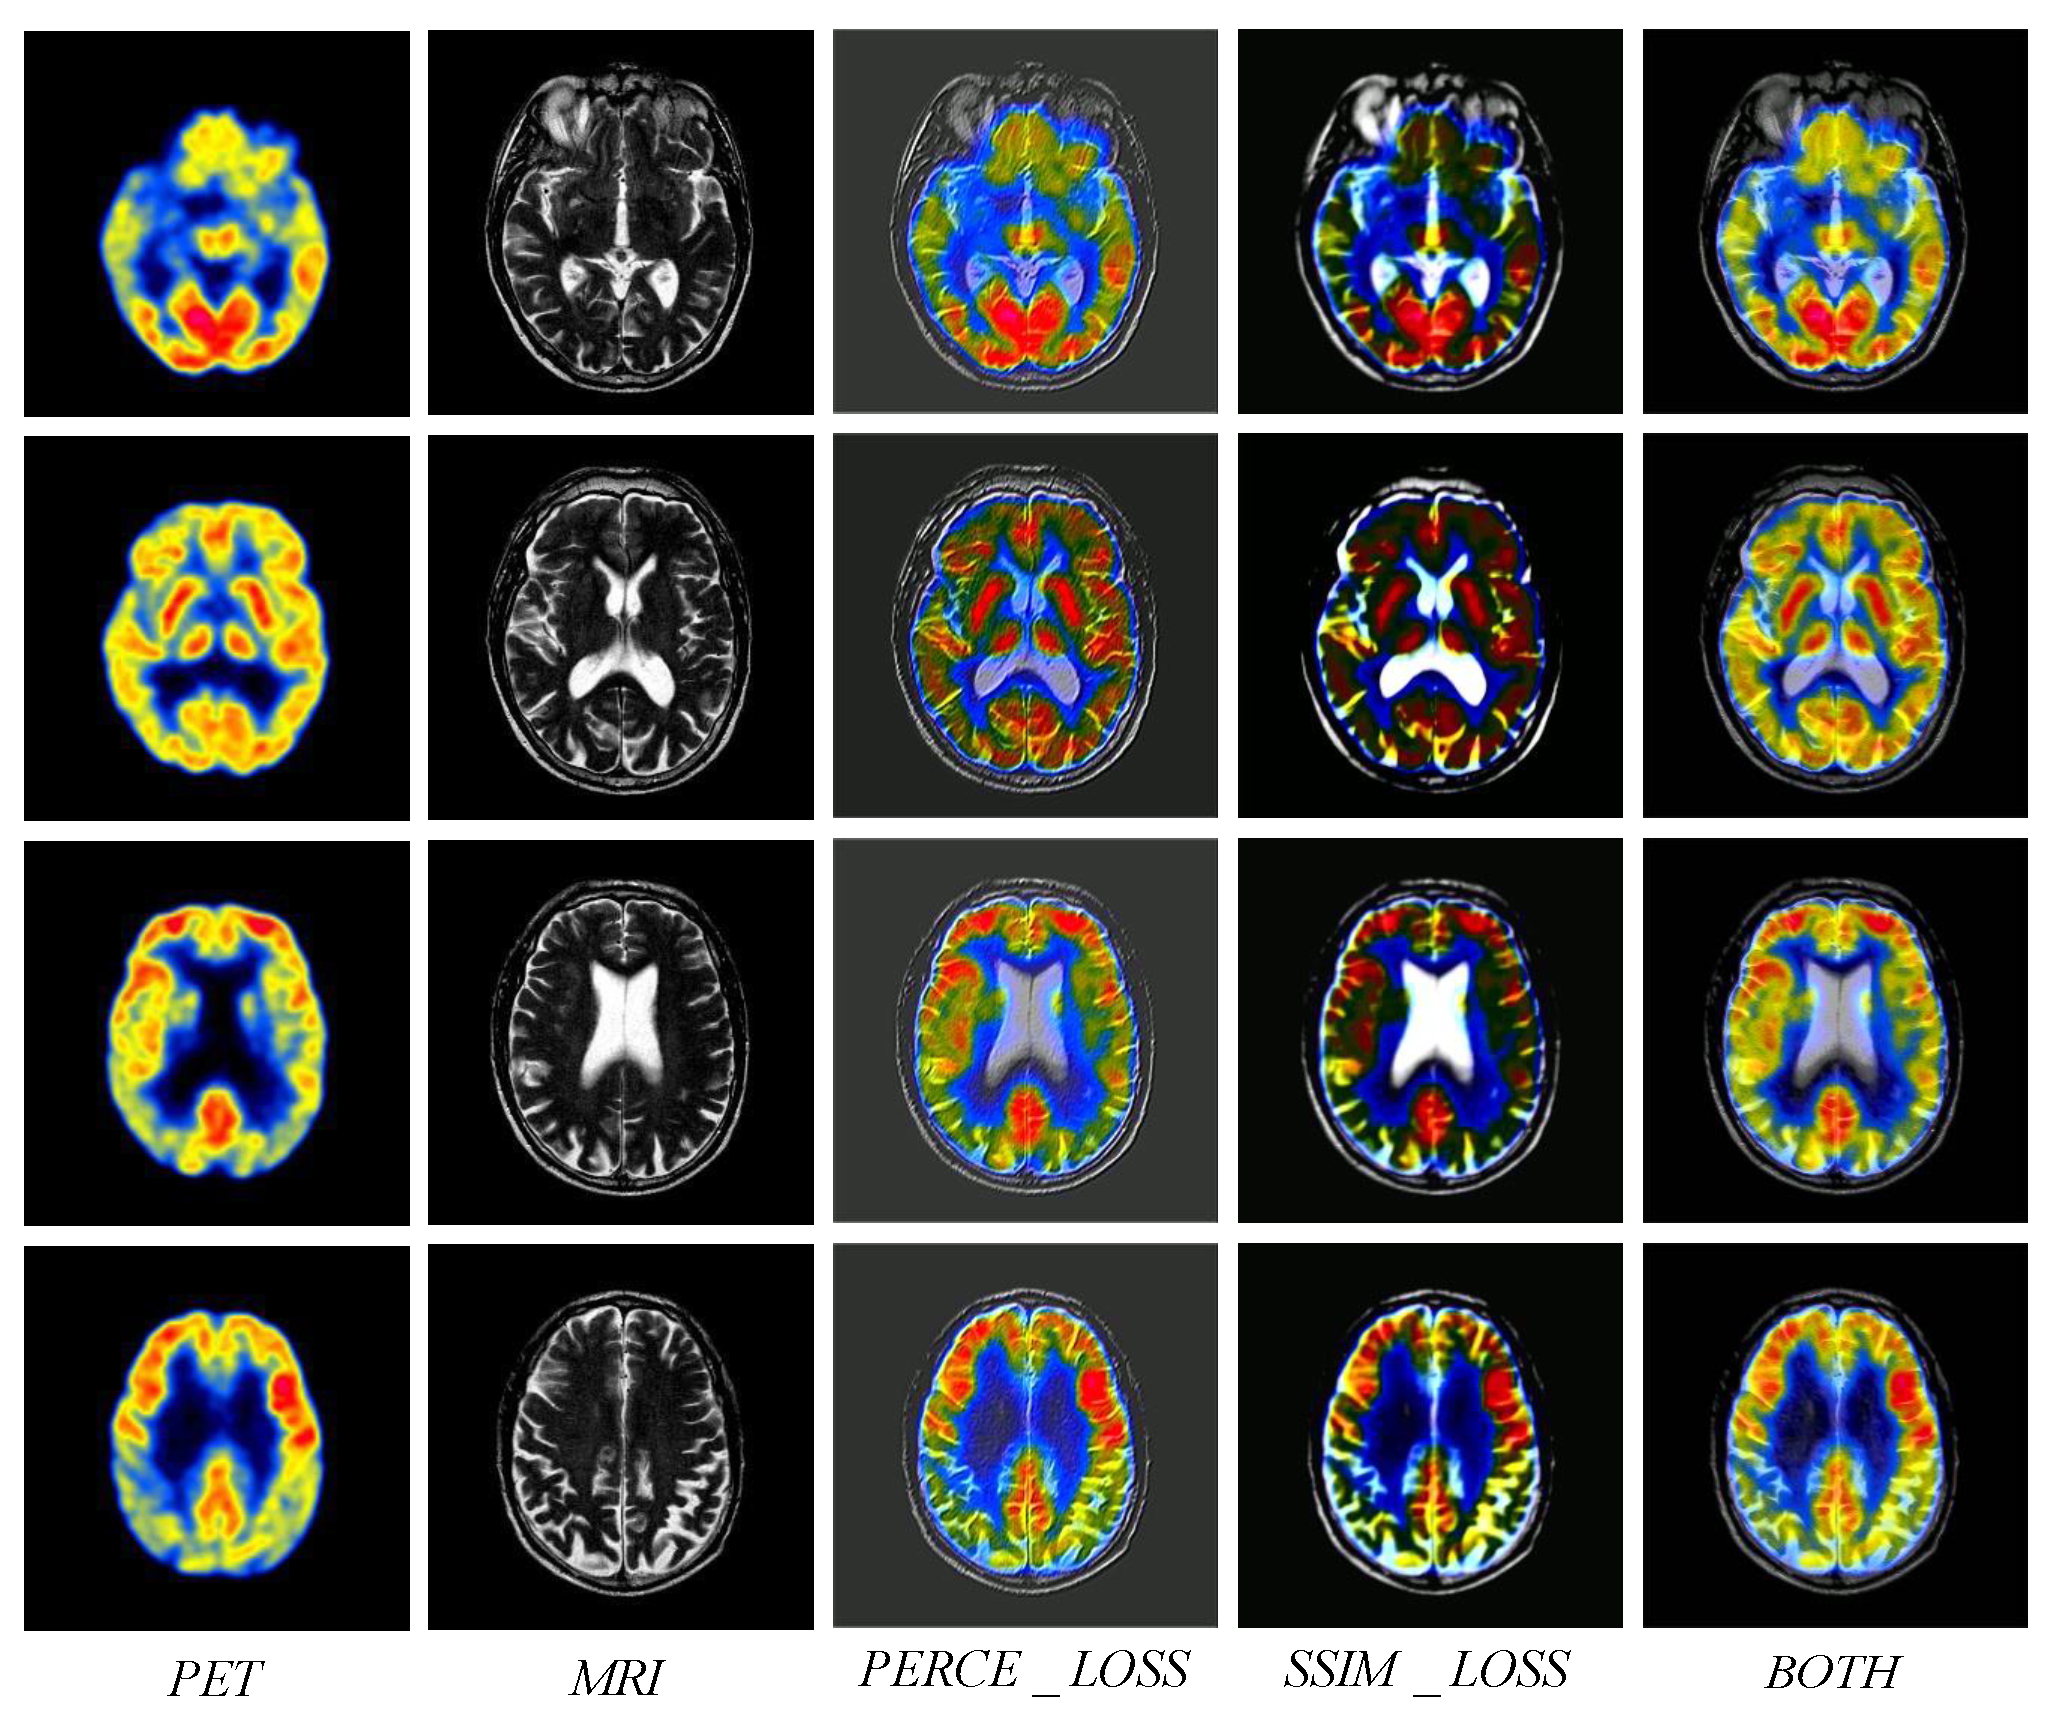

4.3.2. MRI and PET

4.4.1. Ablation Experiment of Loss Function

4.4.2. Ablation Experiment of Network Architecture